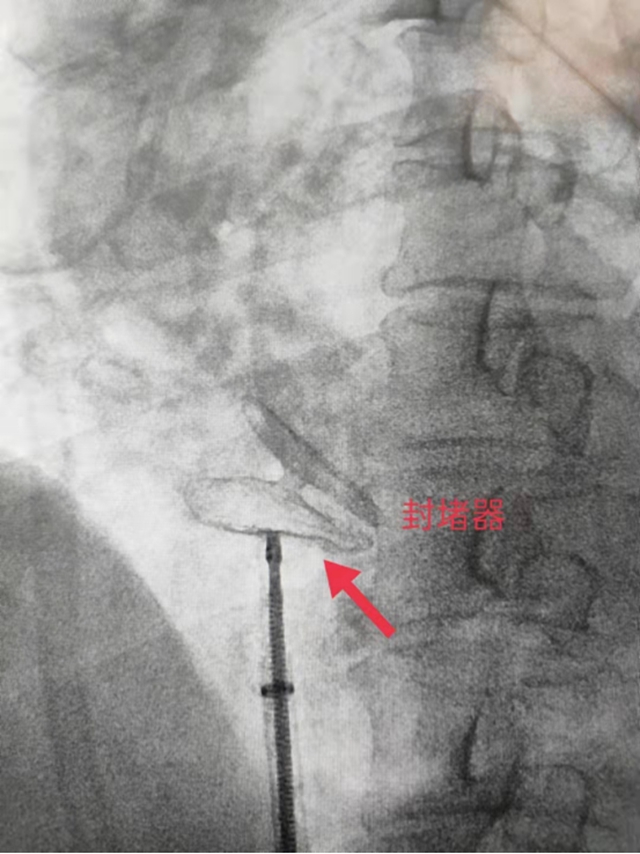

卵圆孔未闭最佳治疗方案——卵圆孔封堵术。此手术是在进行局部麻醉后,通过股静脉置入导管,然后经过下腔静脉、右心房,通过卵圆孔到达左心房,在鞘管内释放封堵伞、回抽,另一侧在右心房内释放,卡在房间隔上。在郑州大学第二附属医院介入科许立国教授、心脏外科周玉阳教授的带领下,商城县人民医院神经内科介入团队已成功开展卵圆孔封堵术10例。